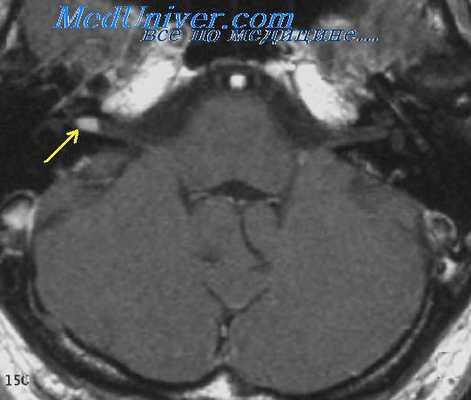

- МРТ показана при наличии очаговой неврологической симптоматики или у пациентов с факторами риска цереброваскулярной патологии